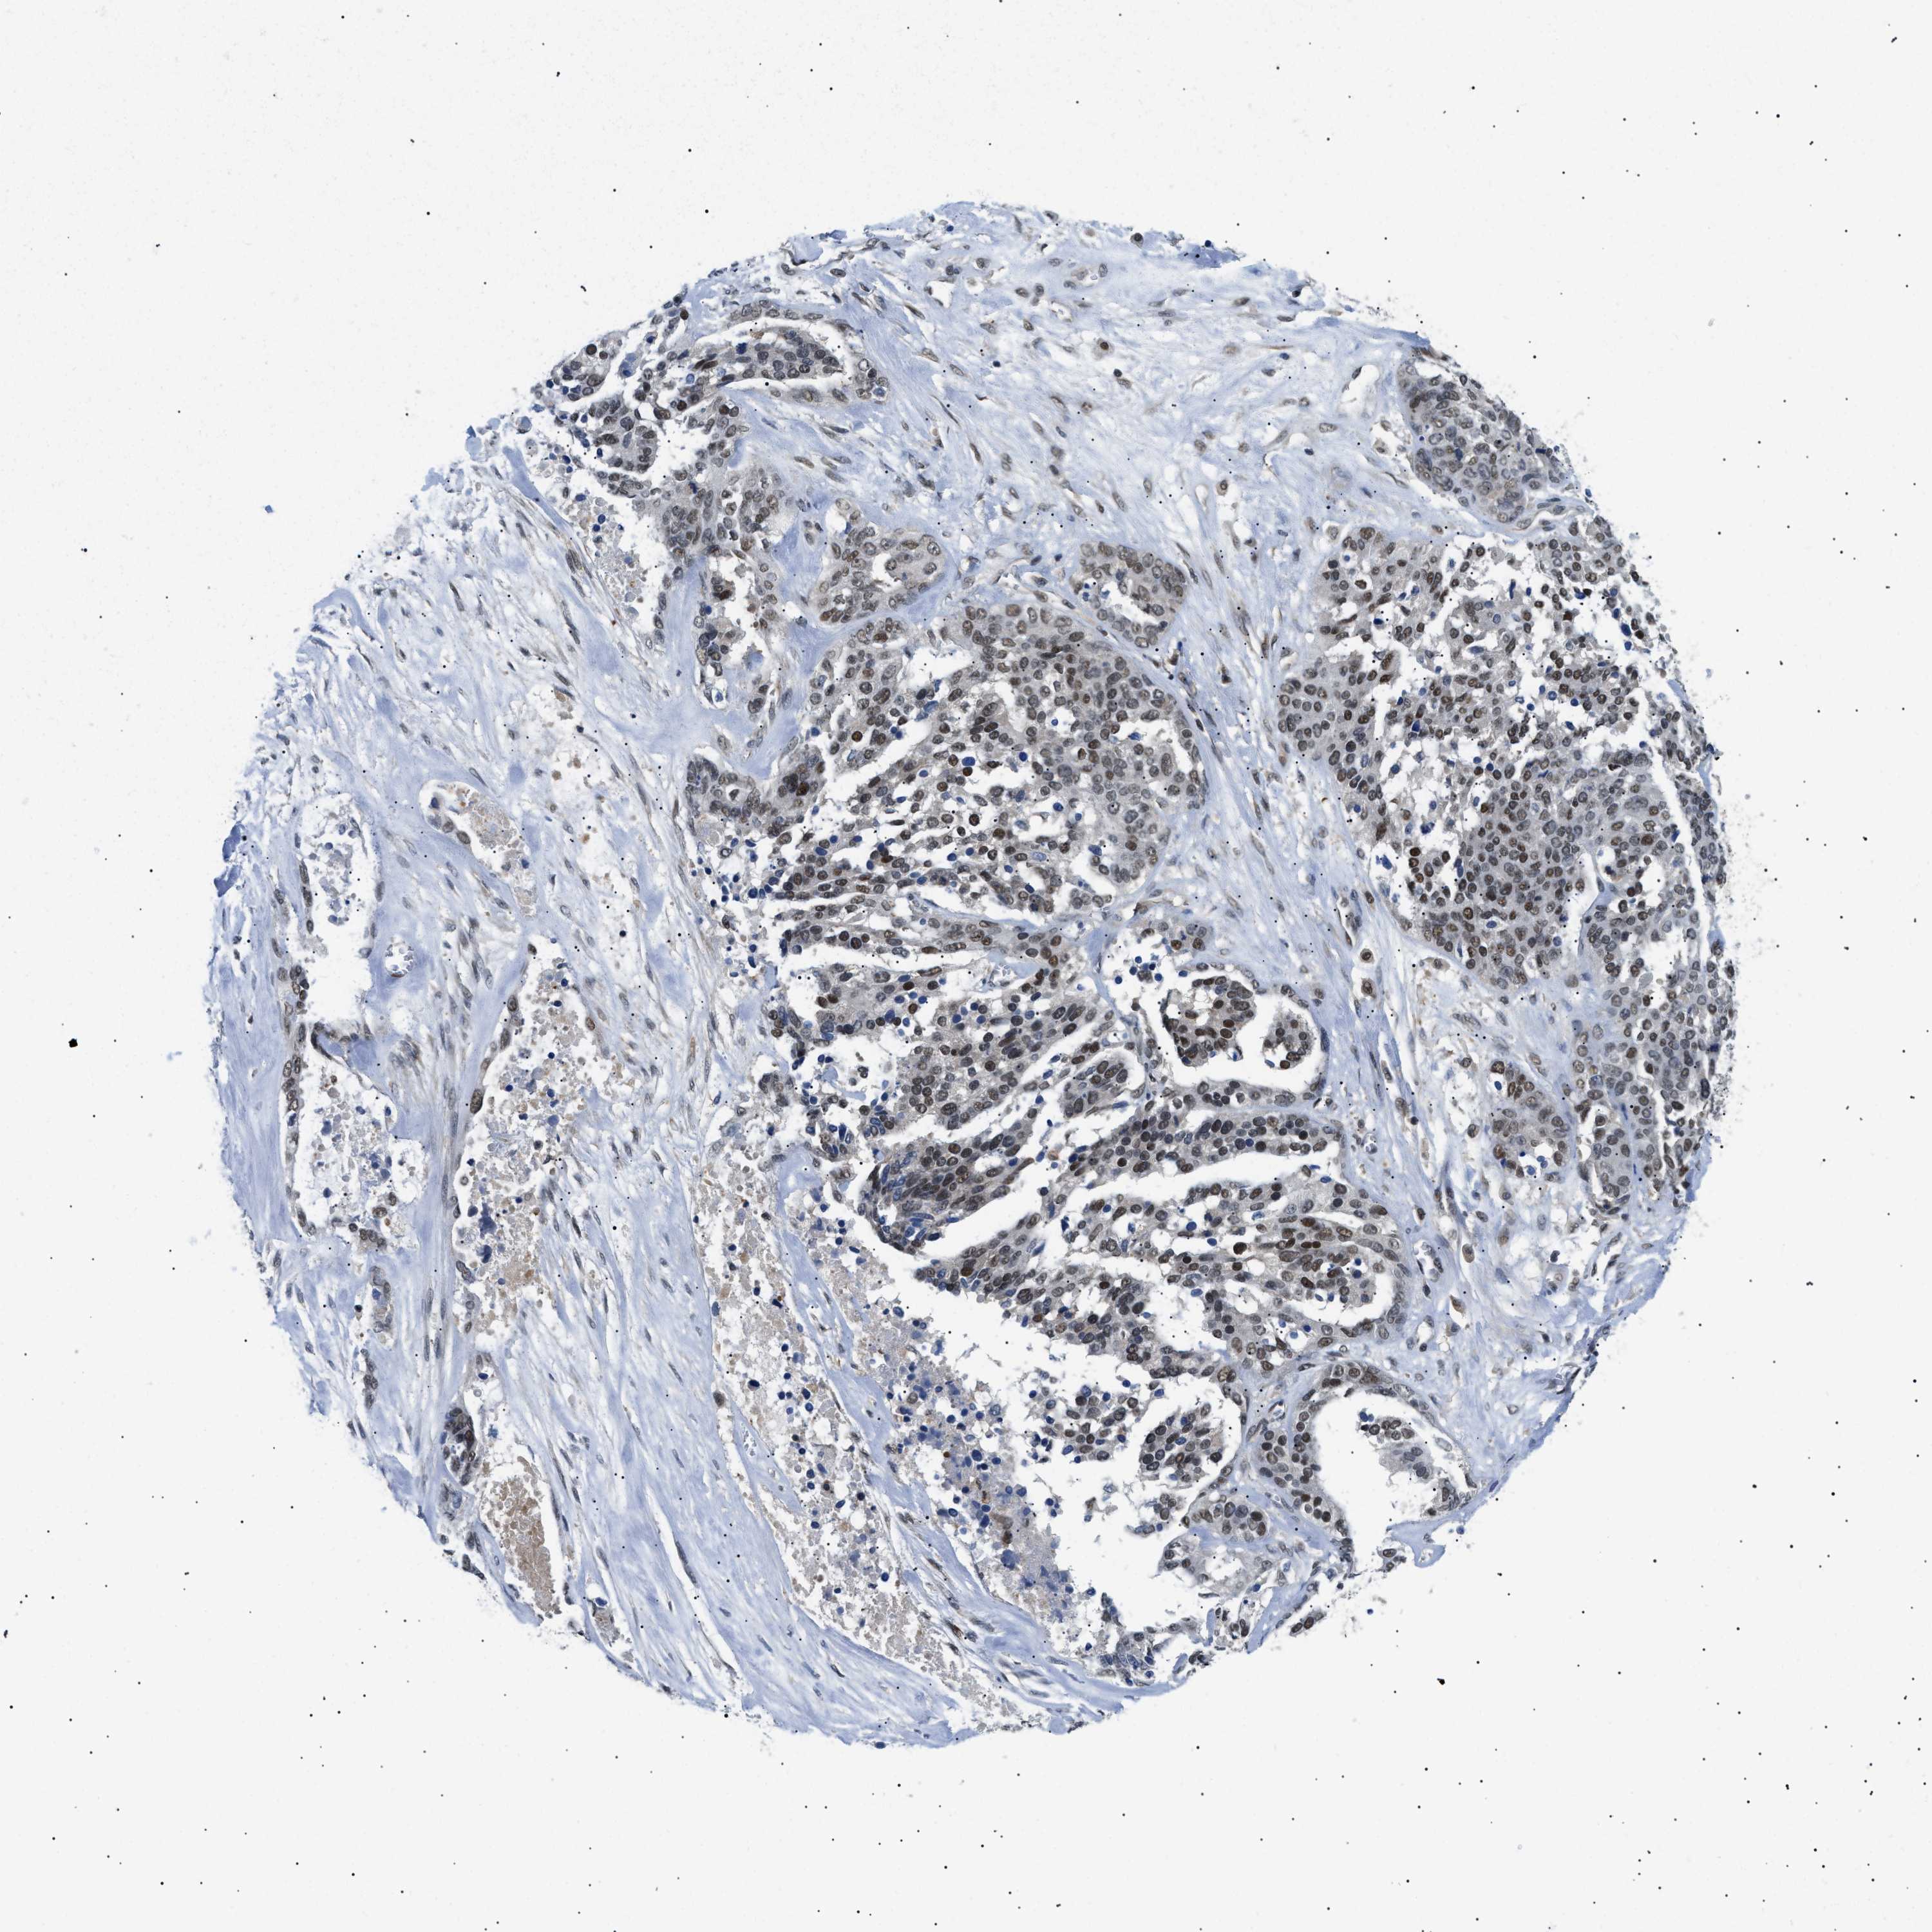

OVARIAN CANCER - Protein expressioni

A mouse-over function shows sample information and annotation data. Click on an image to view it in a full screen mode. Samples can be filtered based on level of antibody staining by selecting one or several of the following categories: high, medium, low and not detected. The assay and annotation is described here.

Note that samples used for immunohistochemistry by the Human Protein Atlas do not correspond to samples in the TCGA dataset.

Antibody stainingi

Antibody staining in the annotated cell types in the current human tissue is reported as not detected, low, medium, or high, based on conventional immunohistochemistry profiling in selected tissues. This score is based on the combination of the staining intensity and fraction of stained cells.

Each image is clickable and will lead to virtual microscopy that enables deeper exploration of all samples and also displays staining intensity scores, fraction scores and subcellular localization as well as patient and tissue information for each sample.

Antibody HPA019824

Antibody CAB015201

Staining

High

Medium

Low

Not detected

Intensity

Strong

Moderate

Weak

Negative

Quantity

>75%

75%-25%

<25%

None

Location

Nuclear

Cytoplasmic/membranous

Cytoplasmic/membranous,nuclear

Cystadenocarcinoma, serous, NOS

Carcinoma, endometroid

Cystadenocarcinoma, mucinous, NOS

Carcinoma, NOS